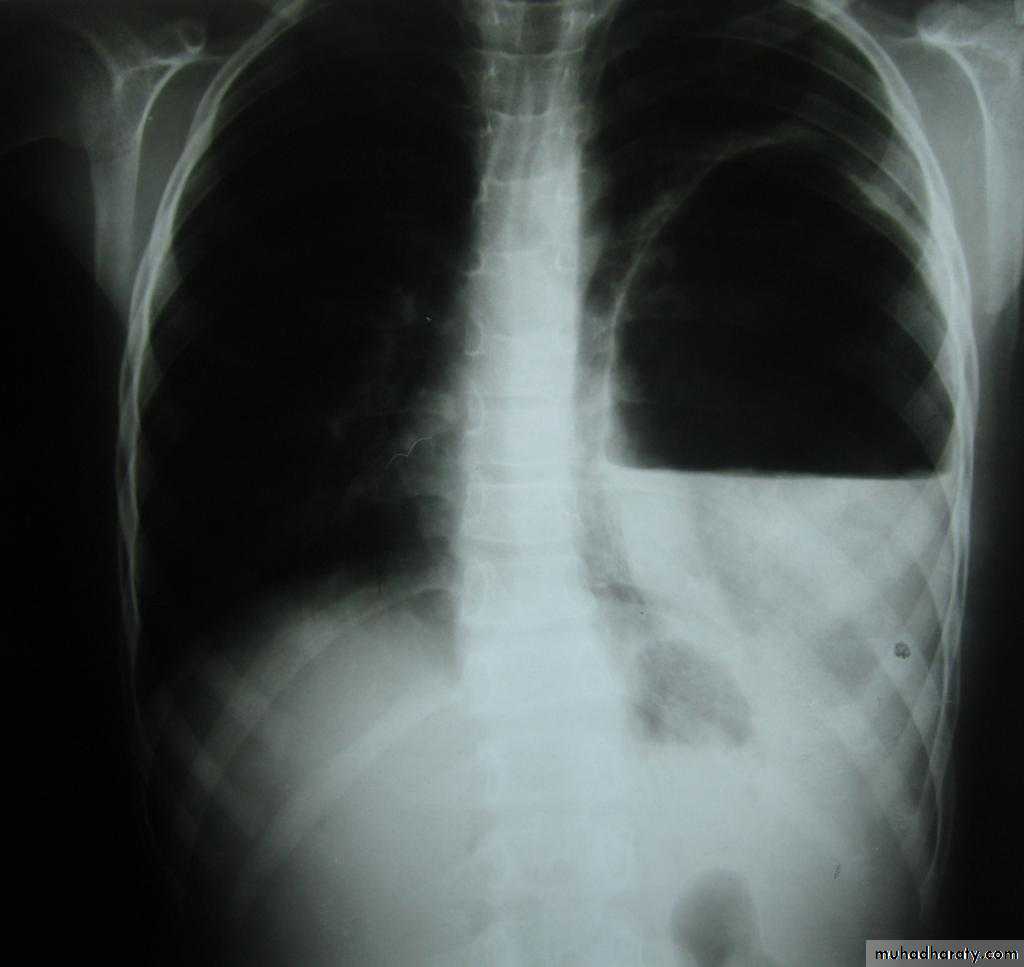

X-ray tension pneumothorax

X-ray pneumothorax